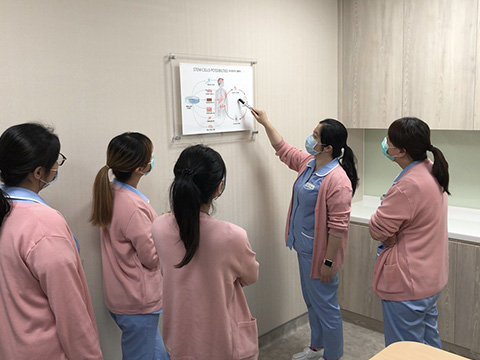

雅斯翠醫療集團秉持著愛與關懷,為國內外患者提供全方位諮詢與治療。擁有英國倫敦帝國學院 Imperial College London 醫學院、德國馬堡大學 Philipps-Universität Marburg (Germany) 醫學院、台大醫院以及高雄醫學大學之專科醫療團隊,同時結合癌症基因來提供個人化精準醫學治療。我們積極培育癌症治療人才,延請國內外多位博士、碩士研究人員,從事各種先進治療、局部動脈化療與基礎醫療研究,推動各項先進醫療技術。

除了專業的手術室、留觀室、恢復室,門診更規劃了能提供病患與家屬溫馨及舒適的就醫環境,包括獨立的病患及家屬等待區、門診化療區、獨立治療空間,可充分保護病患隱密性。期望在舒適、幽靜、清新的環境中讓每位病患得到最佳診治並感受到最溫馨與關懷的照護。

高雄-左營院區